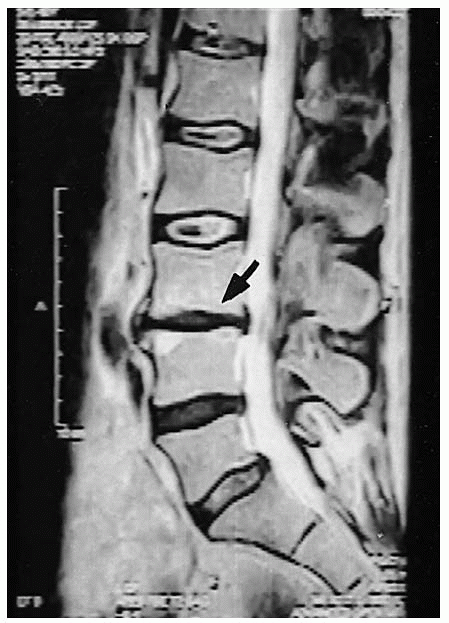

![]() |

FIGURE 19-6. Preoperative T2-weighted sagittal magnetic resonance imaging. At L3-4, note decreased disc height (arrow), decreased signal, and endplate changes.

confirm the correct vertebral level or levels of fusion and to localize

the incision. Anteroposterior (AP) and lateral radiographs (Figs. 19-4 and 19-5), as well as axial computerized tomography (CT) or magnetic resonance imaging (MRI) (Figs. 19-6 and 19-7)

diminished signal on the T-2 weighted image indicating disc desiccation (Fig. 19-6).

Plain radiographs, in the anteroposterior and lateral projection, of